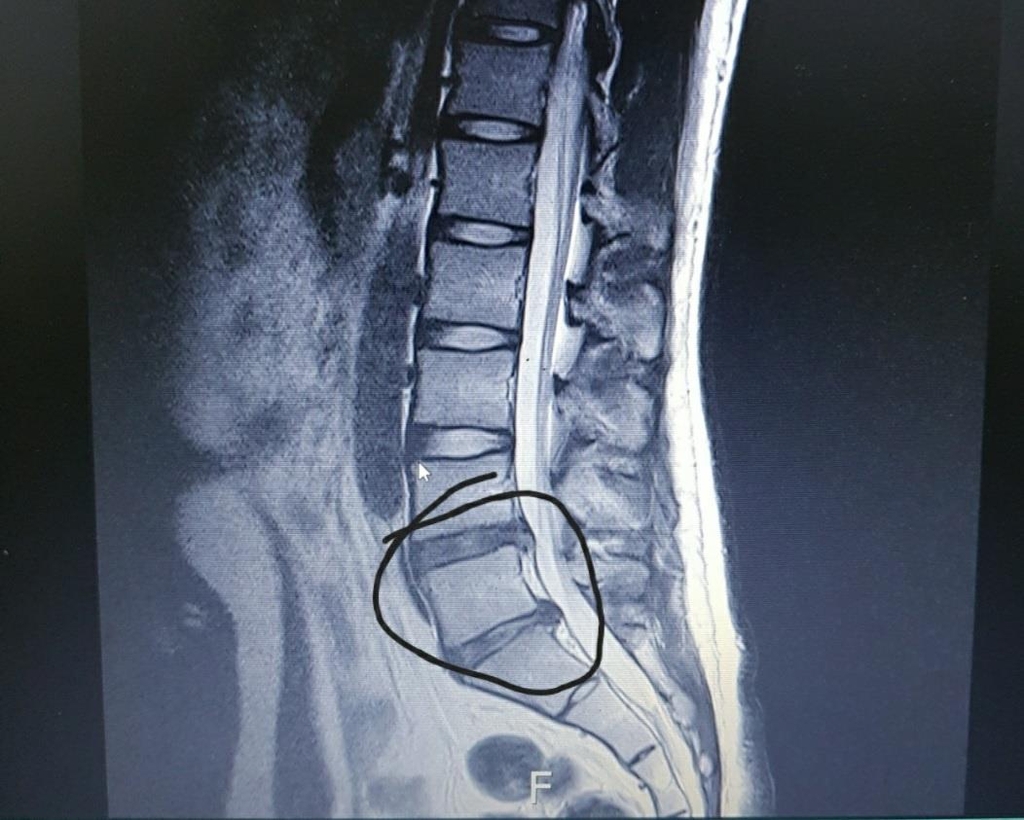

척추와 뼈 사이에 위치한 이 디스크는 외부로부터의 물리적 충격을 완화하고 단단한 뼈가 직접 충돌할 때 문제가 발생하지 않도록 하는 탄성이 높은 구조입니다. 외부의 영향이나 잘못된 위치로 인해 디스크가 꺼지면 염증이 발생하고 신경이 눌려 요통과 요통이 발생합니다. 기술적으로는 요추 디스크 분리라고 하며 일반적으로 요추 디스크 고장이라고 합니다.

허리디스크 진단법